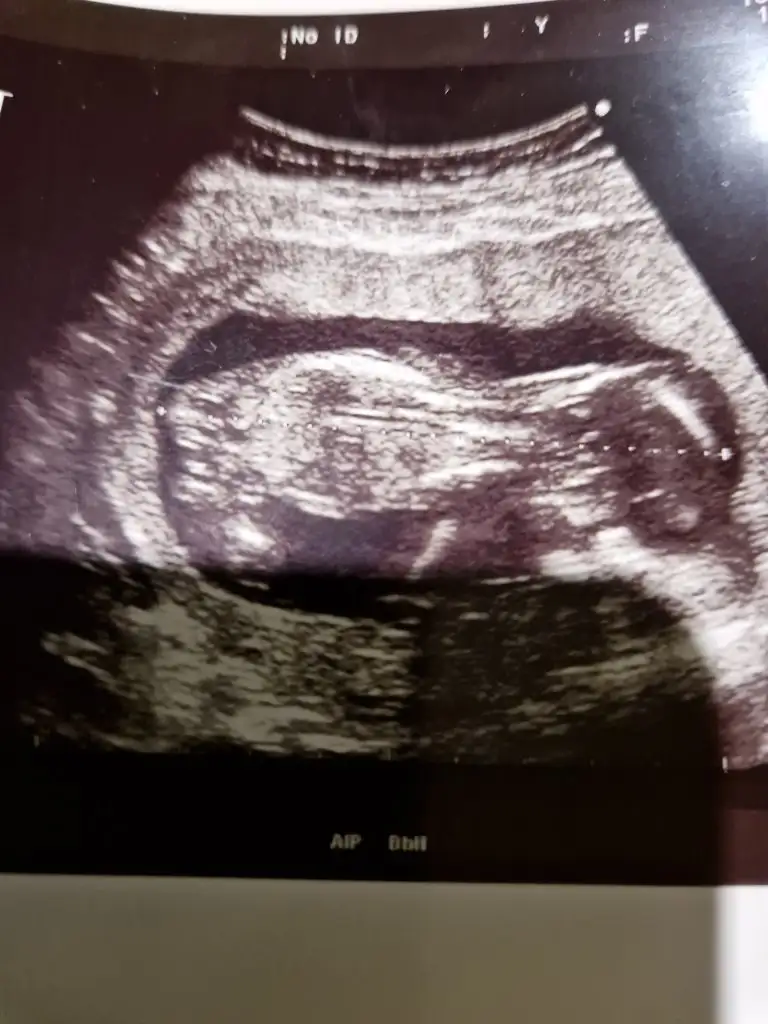

Nub teoriye göre bakarmisniz?

Bu resm

Eklentiler

• 16968682069364493656588897443361.webp

40,4 KB · Görüntüleme: 65